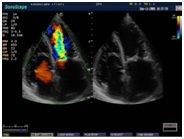

Компания SonoScape уделила особое внимание допплеровским режимам и является экспертом в своем классе, что позволяет с легкостью, но в то же время с уникальной точностью проводить исследования с постановкой наиболее точного диагноза.

Ультразвуковые исследования, доплеровское сканирование сосудов в Медицинском центре «АКВА МЕД МАРИН» выполняется при помощи первого и единственного аппарата в Керчи SonoScape S40Exp (экспертного класса, который оснащен множеством новейших функций, многократно улучшающих качество и информативность УЗИ-исследования).